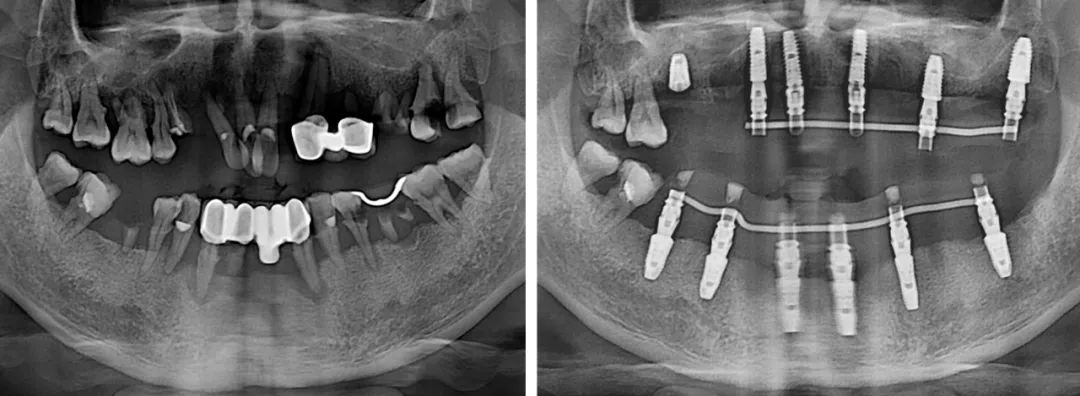

短短幾年,劉今朝已完成種植修復治療上千例,成長速度比絕大多數同齡醫生更快。工作以來,他已多次公派參加專業培訓和學術會議,同時,也完成了從常規種植到半口全口無牙頜種植的技術進階。

“做種植牙,良好的咬合是最終目的。相對單顆、多顆種植,半口咬合重建難度更大。半口種植的患者往往對側牙齒也不是特別好,種植后如何調整咬合,非常考驗醫生的水平。”

技術進階,意味著難度也有了進階,不管遇到什么樣的病例,劉今朝始終牢記“修復是種植的目的”這一原則,以最終的修復效果為目標,來指導整個治療。